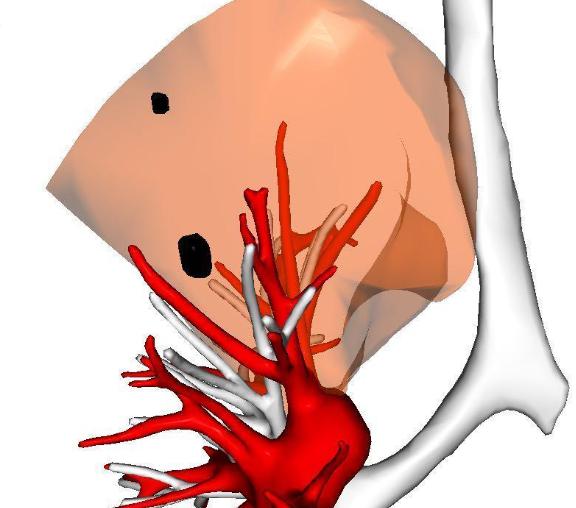

为了一个6mm的小结节,切掉一大块肺?如果是这样的手术,我坚决不做!今年38岁的吴女士体检发现了肺磨玻璃结节,虽然随访了一年都没变化,但问了好几位医生,大多提醒她:“结节中间有空腔,有一定风险,可能是肿瘤特征,建议手术切除肺叶。” 这句话让她陷入了长期的焦虑。那段时间,她吃不下、睡不好,连孩子都顾不上管,甚至出现了胸背痛、气促的症状,整天担心自己是不是晚期了、结节是不是要转移了。 后来她找到我,态度非常坚决:一定要手术,不管切多少肺都愿意做。 但我仔细看了她的片子,结节位置比较深,如果按常规做法切掉整个肺叶,对肺功能的影响不小。 所以我一开始还是建议她继续观察——毕竟结节没变化,通常意味着风险很低。 可她和家人反复联系我,几次来门诊,都坚持要做手术。我理解她的心情,这种“身体里有个东西”的感觉,确实像心里扎了根刺。 于是我跟她商量:不如我们做个三维重建,仔细看看结节的位置和血管走向,说不定能设计一个既切得干净、又不用切那么多肺的手术? 毕竟生命不只有长度,生活质量也很重要...... 三维结果出来之后,我发现可以做“亚段切除”——也就是只切除肺段的一小部分,范围非常精准,创伤也小得多。 术后病理结果是“不典型腺瘤增生”还是属于癌前状态。它有可能随着时间慢慢变化,甚至发展成原位癌或早期腺癌,但这个过程非常缓慢,通过定期随访完全可以安全监控。即便有变化再处理,也完全来得及。 而吴女士之前那些胸痛、气短的症状,其实更多是焦虑引起的身体反应。手术后她恢复得很好,查房时她跟我说:“医生,我现在安心了,心里的‘定时炸弹’终于拆掉了。” 通过这个案例,我也想和大家分享两点: 1、对于这种小的磨玻璃结节,定期随访是非常安全的,不必过度紧张; 2、如果实在焦虑到影响生活,可以考虑做创伤小的精准手术,但为了一个小结节去切掉整个肺叶,我个人认为还是要慎重。[玫瑰][作揖]胸外科乔贵宾医生肺结节[超话]